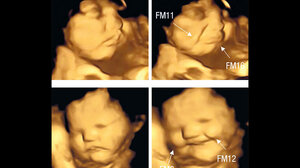

Ήχοι που ακούν τα έμβρυα στην κοιλιά και… μάλλον δεν τους αρέσουν πολύ ΕΚΕΙΝΟΣ & ΕΚΕΙΝΗ 20.07.2025Ήχοι που ακούν τα έμβρυα στην κοιλιά και… μάλλον δεν τους αρέσουν πολύ